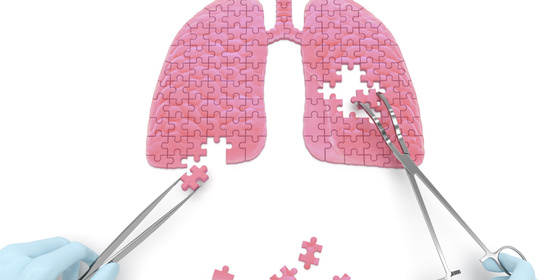

胸麻痺:肋間神經炎、胸椎管狹窄症、肺栓塞、肋膜炎